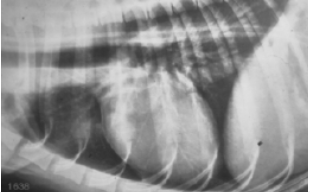

Normal heart